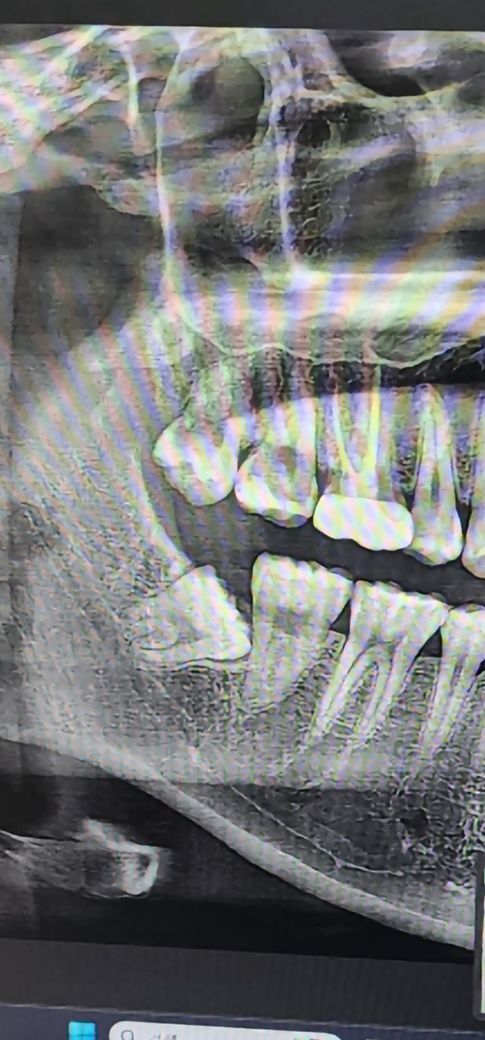

• 2번 째 사진

뽑을 때 위아래 같이 뽑는 것이 좋습니다. 이정도 난이도면 굳이 진정요법 귀찮게 하지 말고 그냥 국소마취만 하고 뽑아도 됩니다. 비용도 더 듭니다.

크게 부작용이 잇거나 그럴만한 사랑니 난이도는 아닌거 같습니다. 치과에 가셔서 편안히 발치를 하시면될것같습니다.

1. 보통은 왼쪽, 오른쪽 한쪽씩 위,아래를 같이 뽑습니다.

2. 사랑니는 보통은 발치 외 별다른 치료를 하진 않습니다.

3. 의식하 진정요법은 큰 부작용 없습니다. 치료 중에 나른해지면서 기분이 좋아지기도 하는데 아마 웃을만한 상황은 못될 겁니다..